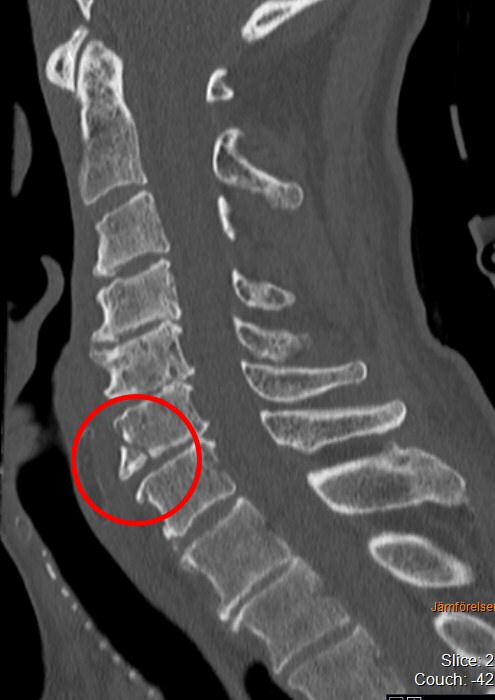

Typiskt äldre patient med degenererad halsrygg som fallit på pannan berusad. DT med diskreta fynd, kan vara helt normal, visa extensions teardrop (se bilder nedan) eller distraktion i disk. Kan vara mycket instabil.

Teardropfrakturer